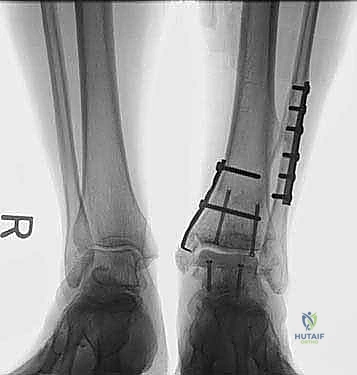

صور إضافية من داخل غرفة العمليات والخطوات الجراحية

ندرك أهمية توثيق الخطوات الجراحية لطلاب الطب والمرضى الراغبين في فهم دقة الإجراء. هذه الصور توضح مراحل زراعة وتثبيت الطعم العظمي الغضروفي بدقة متناهية تحت إشراف أ.د. محمد هطيف.